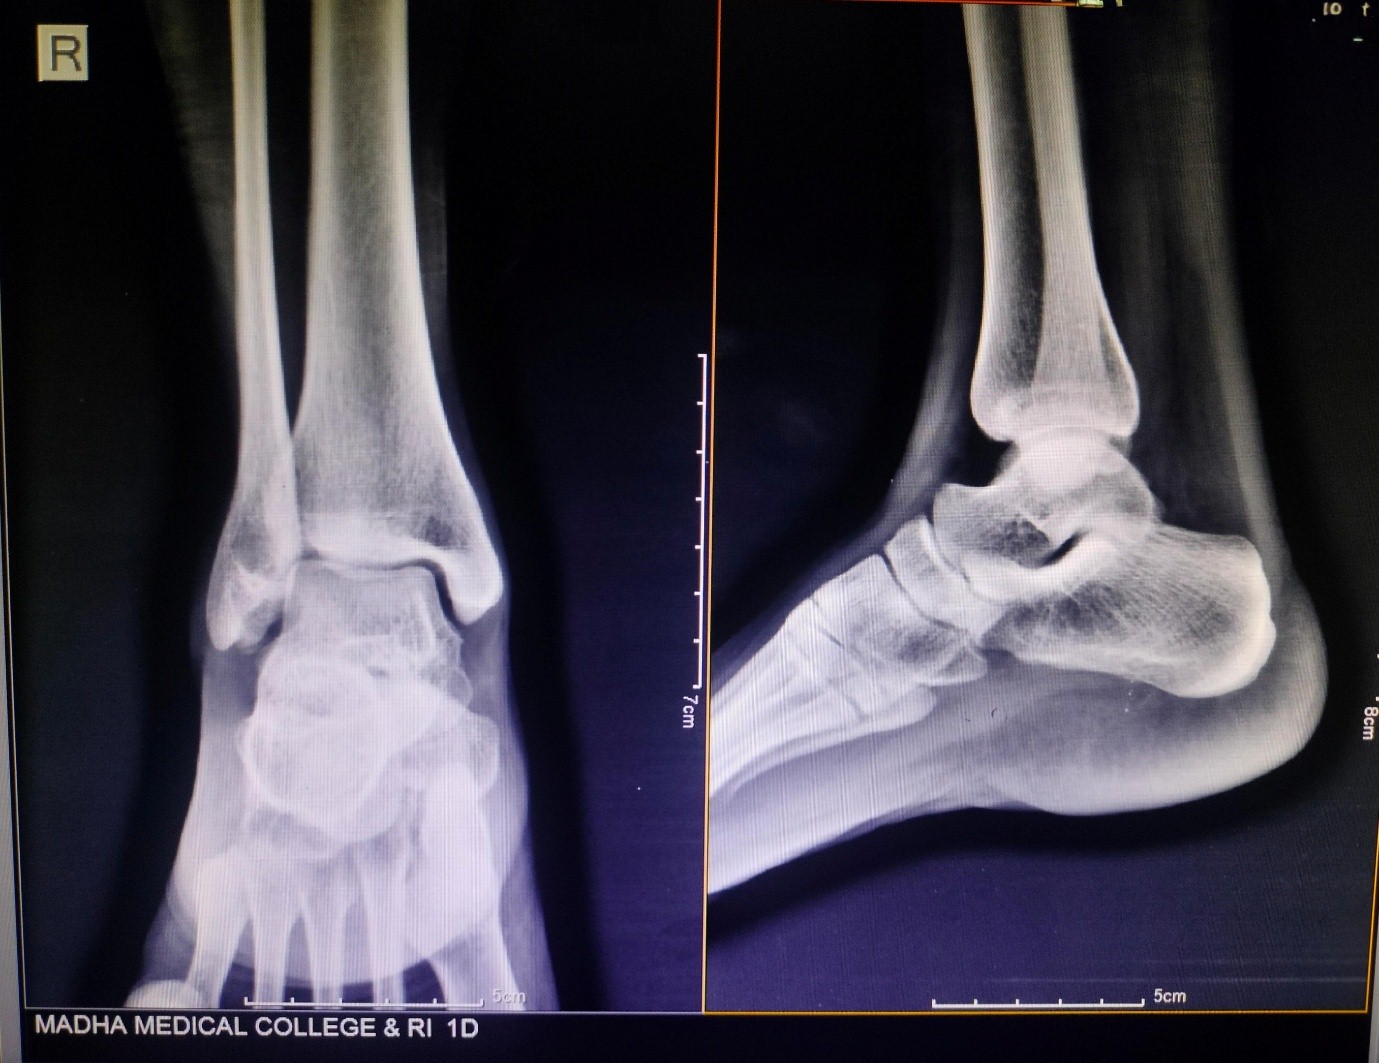

X-rays of the ankle showed a soft tissue bulge near the lateral malleolus, with a few punctate calcific specks – nothing extensive, but enough to suggest loose bodies (Fig. 2). Blood investigations were within normal limits. Based on the location and appearance, SC was kept high on the list. An MRI was done for further clarity. It picked up a subcutaneous swelling with internal areas of low signal, likely calcified, measuring around 2.1 × 0.6 × 1.5 cm, and sitting right over the lateral malleolus. The findings aligned well with what we suspected clinically.

Figure 2: X-ray showing soft tissue bulge near the lateral malleolus, with a few punctate calcific specks.